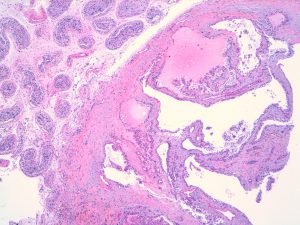

Histological examination showed a partly solid and partly cystic lesion within the paratesticular soft tissue. The cystic spaces showed focal short papillary projections and were lined by cuboidal to columnar epithelial cells with small round nuclei and abundant clear cytoplasm. The supporting stroma was fibrotic. There was no evidence of cellular pleomorphism, mitotic activity or necrosis. The background testicular parenchyma showed seminiferous tubules with active complete spermatogenesis and no evidence of intratubular germ cell neoplasia.

Papillary cystadenoma of the epididymis is an uncommon benign epithelial tumour, which originates within the head of the epididymis and broad ligament. These lesions usually present as paratesticular masses or as an incidental finding detected during fertility workup. The tumour cells have the same immunophenotype as clear cell papillary renal cell tumour, being positive for PAX8, CK7 and CAIX (cup shaped). Papillary cystadenomas of the epididymis can be sporadic or syndromic and bilateral cases have been associated with von Hippel Lindau disease (approximately 50% of cases).

Particularly in the setting of Von Hippel-Lindau disease, the main differential diagnosis is with metastatic renal cell carcinoma. Some cases of papillary cystadenoma can very closely resemble clear cell RCC histologically.However, the immunohistochemistry profile of strong positive staining for CK7, negative staining for CD10 and cup shaped staining with Cabonic Anydrase 9 contrasts with the usual clear cell RCC immunophenotype. Papillary cystadenomas of the epididymis are entirely benign but should always prompt the pathologist to suggest the possibility of associated Von Hippel Lindau syndrome. (1–3).